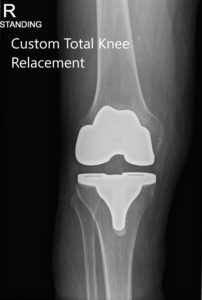

Radiografía postoperatoria de la rodilla derecha del paciente que muestra AP y vistas laterales

El paciente pudo caminar el mismo día después de la cirugía e informó un excelente rango de movimiento de la rodilla en las visitas posteriores. Ella pudo conducir y continuar sus actividades diarias, como caminar, subir escaleras sin dolor después de un período de fisioterapia. En las siguientes visitas postoperatorias posteriores, no informó rigidez en la rodilla derecha con un excelente rango de movimiento. El paciente tuvo una excelente recuperación del dolor de artritis de la rodilla izquierda debido a la descarga de peso de la artroplastia total de rodilla derecha exitosa.